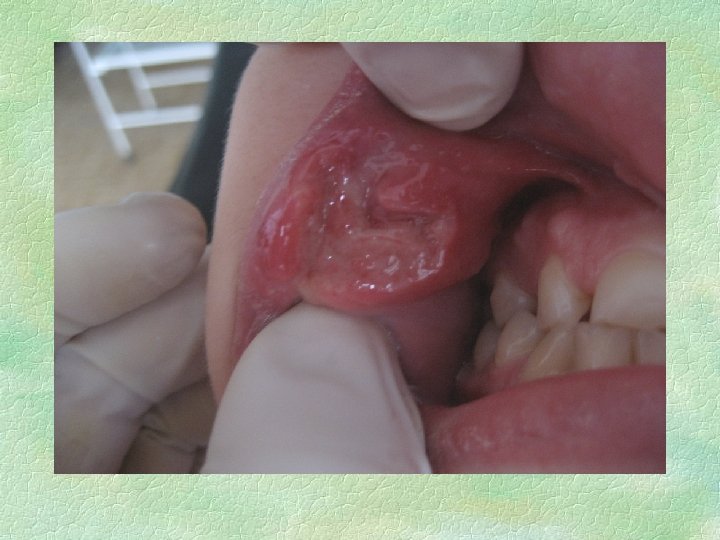

Афта Сеттона § § § § § Чаще у женщин. Возраст начала первичной атаки – 10 -30 лет. Заболевание может начинаться как глубокая язва, но чаще ей предшествует фибринозная форма ХРАС. Частота рецидивов – постоянно; нет периода, когда во рту нет хотя бы одной язвы. Предвестники – чаще парестезия слизистой оболочки, иногда субфебрильная температура, локализованная лимфаденопатия, отек слизистой, чаще языка. Клиническое течение – волнообразное, длительное течение, приводит к существенной деформации слизистой оболочки. Количество элементов – от 2 до 10, редко больше. Ползущая язва характеризуется заживлением на одном полюсе, с ростом на другом. Размер – от 1 см вплоть до поражения значительных участков слизистой оболочки. Локализация – слизистая оболочка, покрытая многослойным плоским неороговевающим эпителием, однако при росте язва может распространяться и на зоны с ороговевающим эпителием. Течение – до полутора месяцев. Заживление происходит с образованием деформирующего рубца.